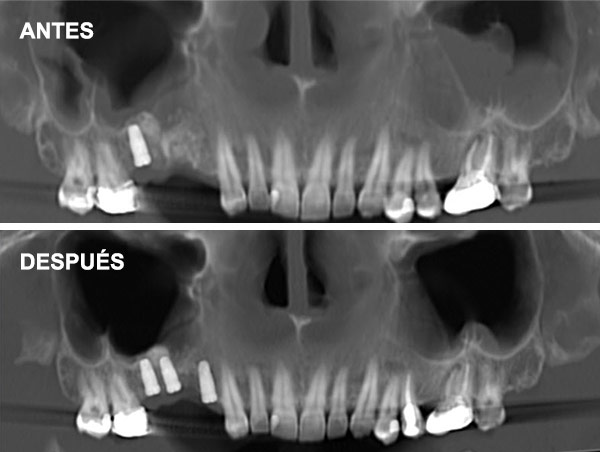

¿Qué es la Elevación Atraumática?

Se realiza a través de la misma osteotomía de colocación del implante, utilizando fresas o dispositivos especiales para levantar la membrana sinusal de manera indirecta.

Indicaciones: Se recomienda cuando existe una altura de hueso residual moderada (alrededor de 5-8 mm) y el aumento necesario no es muy grande.

Es menos invasiva, con una recuperación más rápida y menor riesgo de complicaciones y molestias postoperatorias.